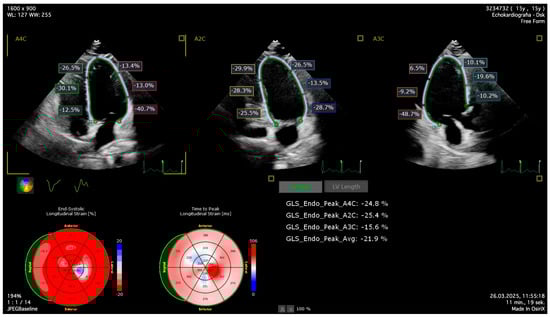

| LV-GLS-2D (%) | −24.6 ± 3.3 | −21.0 ± 3.3 | <0.001 t* | −3.5 (−5.1/−1.8) | −0.865 cd |

| 3D Echocardiography | |||||

| LV-GLS-3D (%) | −23.3 ± 5.3 | −20.4 ± 2.8 | 0.03 t* | −2.1 (−4.9/0.7) | −0.756 cd |

| LV-GCS-3D (%) | −26.3 ± 5.9 | −21.9 ± 3.2 | 0.02 t* | −3.8 (−6.8/−0.8) | −0.555 cd |